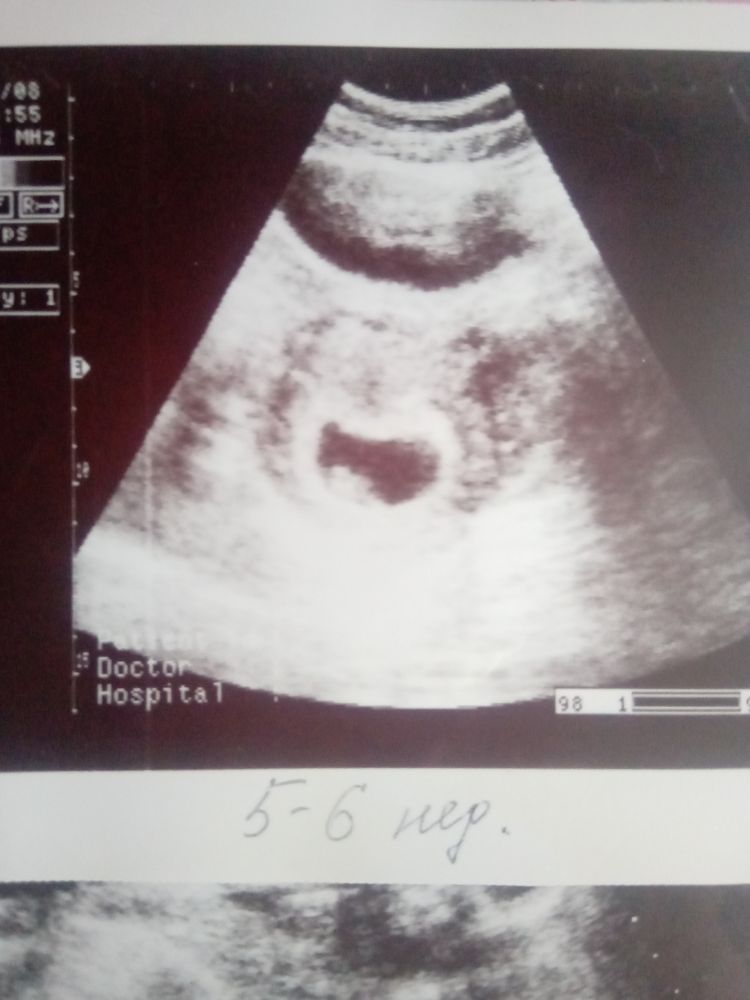

Вот третья и четвертая в 7 нед 👆

Вот вторая дочка 5-6 нед, эмбрион, сб+ 👇